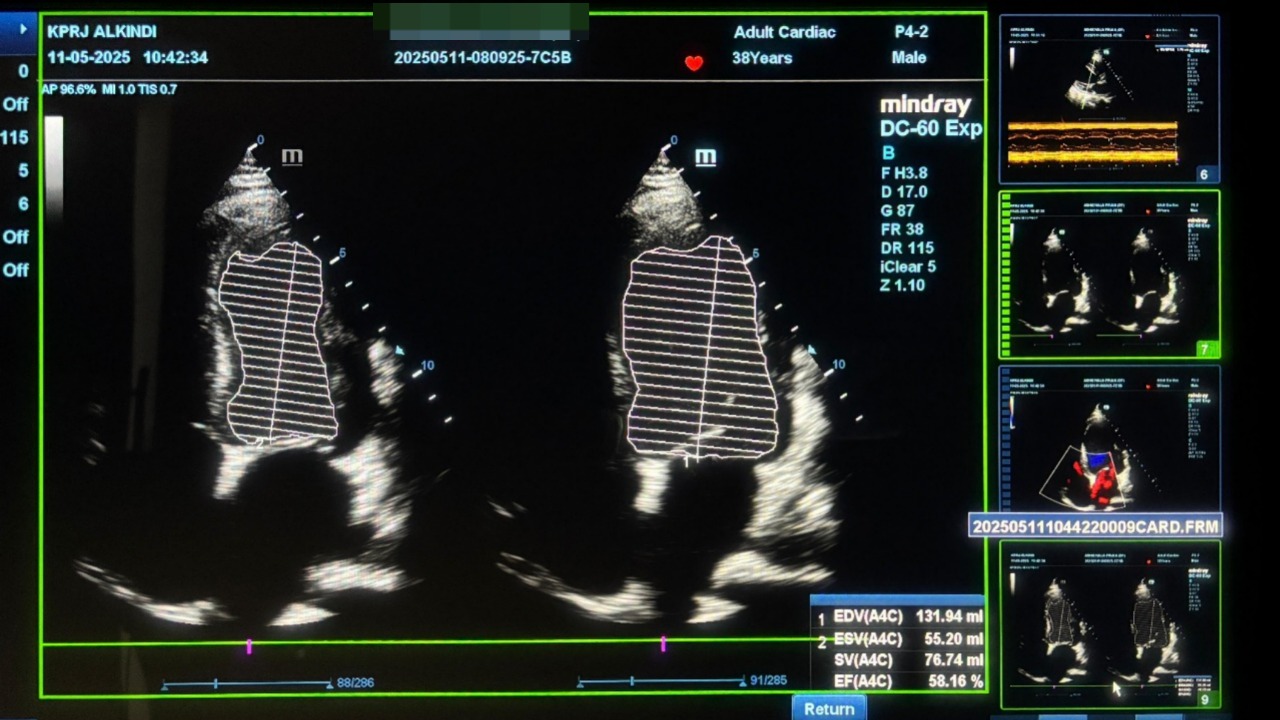

Hasil: EF naik ke 58,16% Subjektif: pasien kembali bisa beraktivitas ringan dan tidur nyenyak Objektif: peningkatan perfusi, pengurangan gejala kongesti, dan tidak perlu operasi

Setelah terapi Program Cardiacsave

Pada pemeriksaan Echocardiografi EF membaik signifikan menjadi 58,16% (11-05-2025)

Menunjukkan pemulihan fungsi miokardial, peningkatan perfusi jantung, dan perbaikan pompa jantung tanpa prosedur invasif.